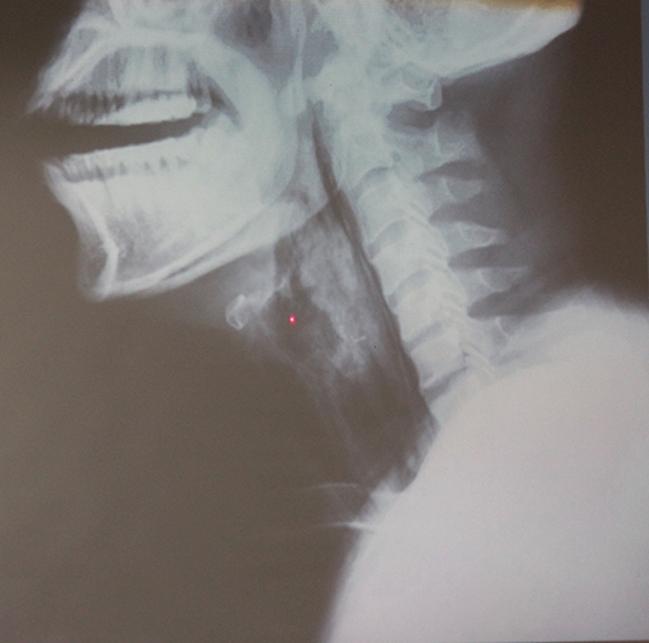

Cổ họng anh D. bị phù nề và tổn thương nặng vì bệnh viêm thanh thiệt cấp.

Sau khi làm các xét nghiệm, các bác sĩ phát hiện, anh D. không phải bị mắc xương cá như người nhà khai, mà lại bị viêm phù nề thanh thiệt cấp. Đây là căn bệnh nguy hiểm có thể lấy đi tính mạng chỉ trong một giờ nếu bệnh trở nặng.

Một người bị viêm “nắp” thanh quản cấp phù nề thì “nắp” thanh quản không thể “bật” lên, nó đóng chặt khiến bệnh nhân không thể thở được, gây suy hô hấp.

Bệnh nhân có thể tử vong trong vòng 30 phút đến 1 tiếng nếu không được phát hiện và cấp cứu kịp thời”.

Nắp thanh quản.